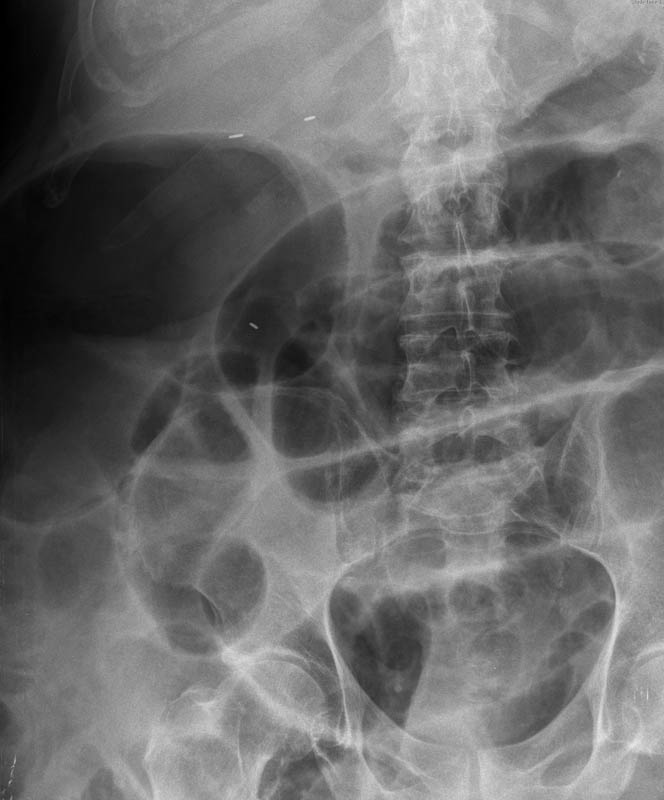

Suboclusión intestinal.